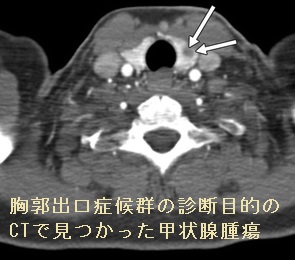

胸郭出口症候群は、睡眠障害、女性ホルモン(エストロゲン)欠乏、甲状腺機能低下症、関節リウマチ、線維筋痛症、脊柱側弯症などの姿勢障害で悪化します。

しかし、甲状腺腫瘍・甲状腺癌で胸郭出口症候群を起こした報告はありません。胸郭出口症候群の診断目的のCTで、偶然、甲状腺腫瘍が見つかった報告はあります(AJR Am J Roentgenol. 2010 Nov;195(5):1066-71.)。